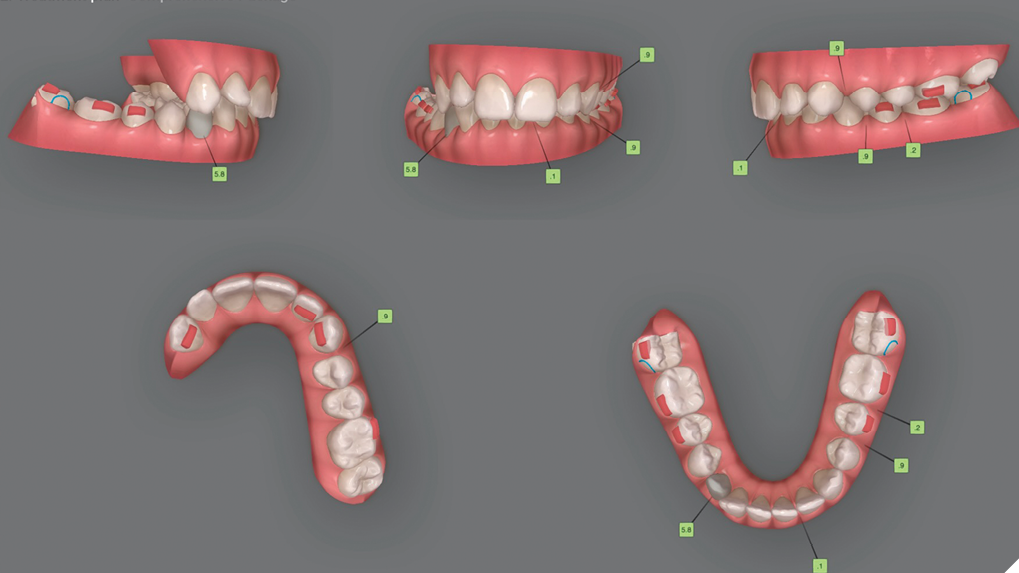

Treatment of a class II subdivision and impacted canine with Clear Carriere Motion2 and Invisalign simultaneously

This is “The most elegant way to correct class II cases” and treat an impacted canine simultaneously. I have personally met Dr. Luis Carriere and his father, Pepe (PHD in Orthodontics), at their Barcelona’s Clinic in September of 2016 to learn more about his unique approach and thinking of implementing invisalign at the same time … Read more